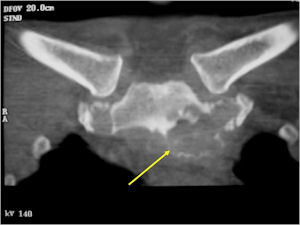

- Spine (40% of cases; usually posterior elements)

- Geographic, circumscribed lesion usually around 5cm in size.

- There may be expansion of bone, cortical thinning and cortical breakthrough. A soft tissue mass may accompany this lesion but the soft tissue component is usually contained by the periosteum.

- The periosteum remains intact around the soft tissue component. Might need a CT scan to detect the subtle calcification (Egg Shell Rim of Calcification) associated with an intact periosteal reaction

- More useful for detecting mineralization and evaluating extent of bone destruction than plain X-ray